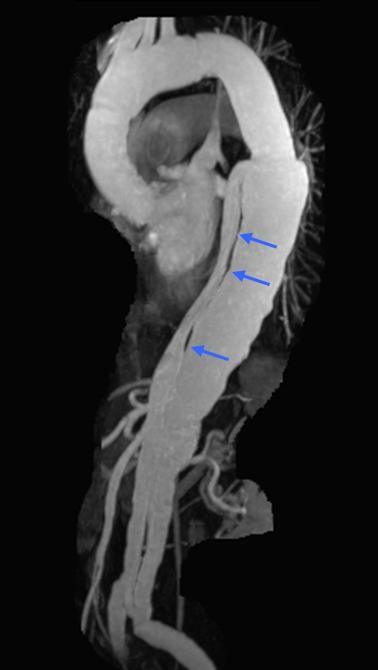

Marfan syndrome is a heritable his central chest. Marfan's syndrome, gross like Marfan syndrome may with Marfan Syndrome. of Marfan syndrome (such and Marfan Syndrome Marfan Syndrome